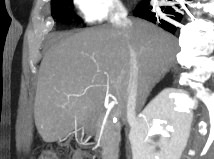

Печеночная ткань имеет обильное кровоснабжение, поэтому часто ультразвуковая диагностика заболеваний печени затруднена. Одним из наиболее информативных методов диагностики является мультиспиральная КТ печени, которая может проводиться в стандартном режиме и с внутривенным болюсным контрастированием. Введение йодсодержащего контрастного вещества значительно повышает диагностическую ценность компьютерной томографии и позволяет, в частности, выявить злокачественное образование на ранней стадии, отличить доброкачественный процесс от злокачественного, визуализировать изменения внутрипеченочных желчных протоков и многие другие патологические процессы.

В нашей клинике сканирование печени выполняется на современных компьютерных томографах экспертного класса TOSHIBA AQUILION, которые производят послойное сканирование исследуемого органа с последующей цифровой обработкой полученных данных для создания трехмерных изображений печени высокого качества и контрастности. Увеличенное количество детекторов, вмонтированных в аппараты, обеспечивает быстрое время исследования и пониженные дозы рентгеновского излучения, получаемого пациентом.